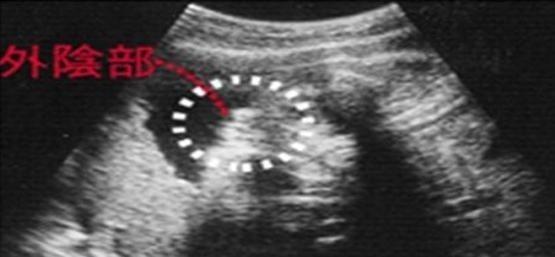

女宝宝的b超图

女宝宝B超

三条白线是明显的女宝特征,如果没有看到明显的三条白线,就看两腿之间有没有突出的东东,且中间有小凹槽的,就是女宝。